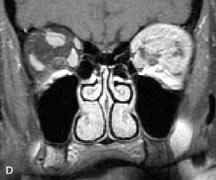

MRI is particularly helpful in the detection and characterization of subperiosteal hematomas of the orbit (Fig. 19). They are most commonly seen in the subperiosteal space of the superior orbit as well-defined masses following a traumatic injury. The signal intensity varies depending on the acute, subacute, or chronic nature of the hematoma, based on the stage of blood degradation. Fresh hemorrhages are hypointense on T1-weighted images and hyperintense on T2 images. Hematomas that are 1 to 7 days old are hypointense on both T1- and T2-weighted images. T1-weighted images of hematomas more than a week old are hyperintense due to the oxidation of deoxyhemoglobin to methemoglobin, whereas the T2 images remain hypointense.63

Fig. 19. A. T1- and (B) T2-weighted MR scans demonstrate a large acute subperiosteal hematoma (H) that lies between the cortical bone of the orbital roof and the inferiorly displaced periorthira (double arrow). The extracopal fat (arrow) and levator muscle are displaced inferiorly.